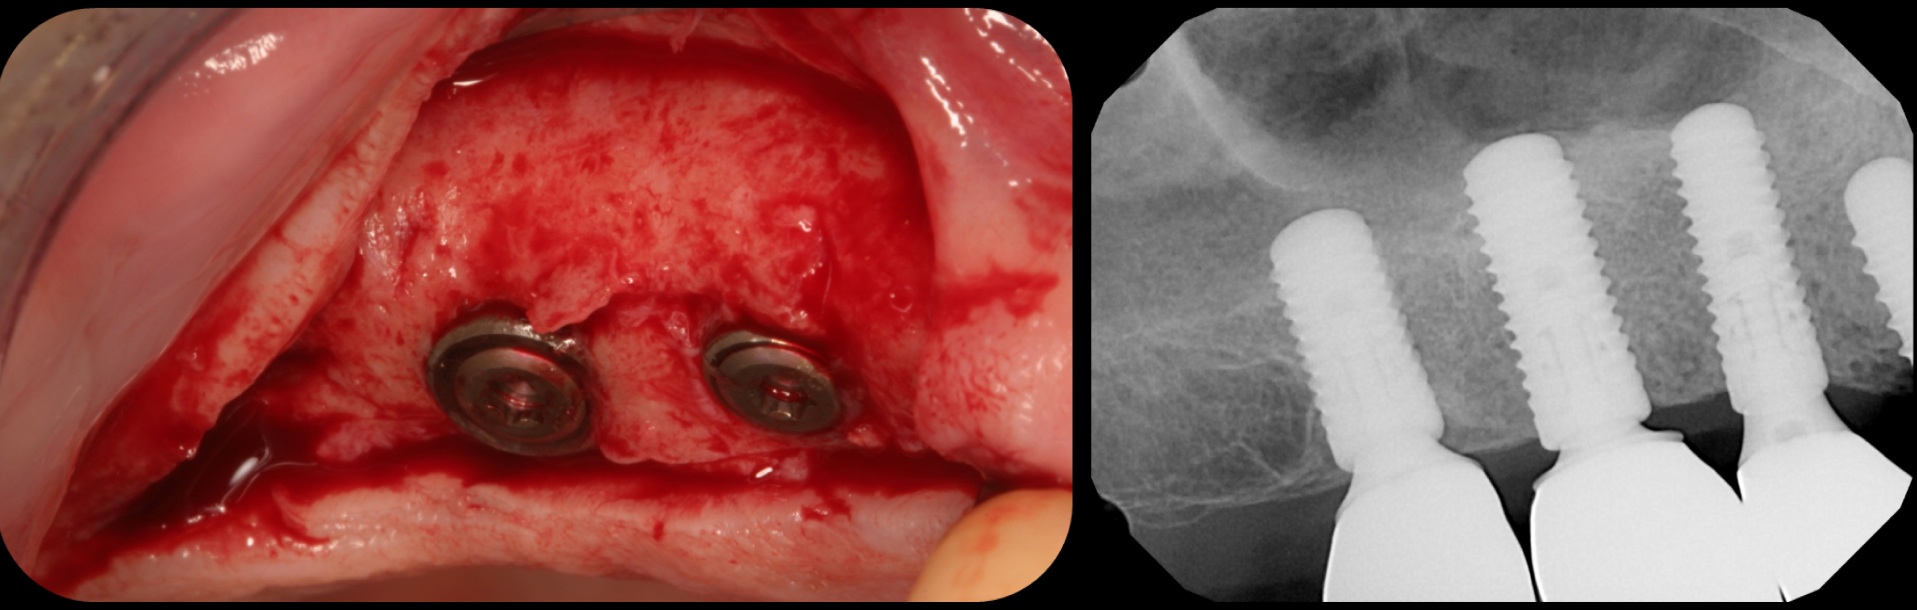

Traditional sinus lift.

Fig. 11

Implants plus BMP without bone graft.

Fig. 12

Bone regeneration and implants loaded in 16 weeks.

Fig. 13